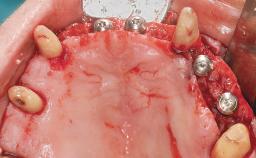

Immediate Loading of Six Implants in the Maxilla and Final Restoration with a Full-Arch CAD/CAM Zirconia FDP

A 63-year-old male patient was referred for a consultation and treatment of partial edentulism in the maxilla. The patient presented with residual anterior teeth and declined a partial removable prosthesis. He reported that the maxillary posterior teeth had been extracted due to mobility and periodontal disease two months before the consultation. The patient’s chief complaint was that his residual maxillary teeth were mobile and that he was unable to chew. The patient’s desire was a stable and comfortable fixed maxillary rehabilitation. The patient was a light smoker (fewer than 10 cigarettes/ day), and his medical history was without significant findings. He was not on any regular medication at the time of consultation. The extraoral examination revealed a normal physiognomy with a correct distribution of the facial thirds. The patient presented a low lip line, and the transition line between teeth and soft tissues was not exposed during a forced smile.

# of Implants 6

Bone Augmentation Horizontal|Simultaneous

Defining Characteristics Fully edentulous upper jaw to be rehabilitated with four or more implants

Modality 6+ implants with immediate loading